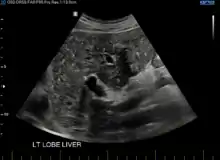

At CT scans, bile duct hamartomas appear as small, well-defined hypo- or isoattenuating masses with little or no enhancement after contrast administration.[3] At MRI, they appear hypointense on T1-weighted images, iso- or slightly hyperintense on T2-weighted images, and hypointense after administration of gadolinium based contrast-agent.[3] On imaging, multiple hamartomas may look similar to metastases or microabscesses.